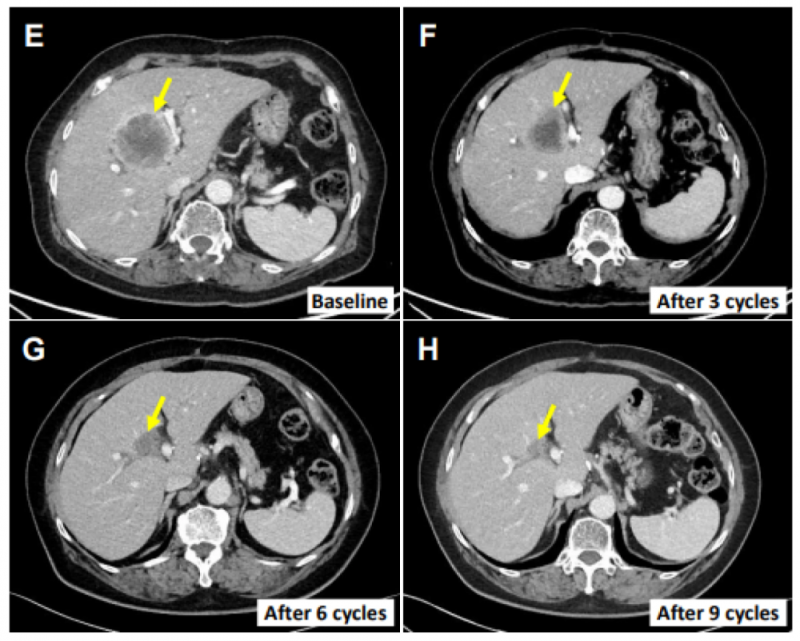

2、患者E0217(76岁女性):确诊为肝外胆管癌,行胆总管节段切除术+胆囊切除术后4个月出现多发肝转移,经吉西他滨+顺铂化疗后病灶持续进展。入组接受SMT-NK联合治疗后,肝转移病灶缩小70.4%(图3E-H),初次治疗后12个月仍无进展。

▼患者E0217的主要肝转移病灶治疗前后对比

▲图源“Cancers”,版权归原作者所有,如无意中侵犯了知识产权,请联系我们删除